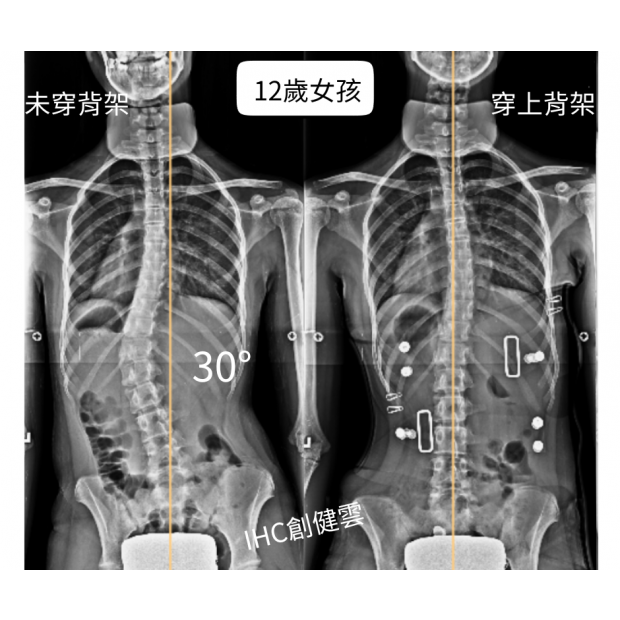

12歲脊椎側彎女孩,腰彎30度

12歲脊椎側彎女孩,腰彎30度 穿上背架後立即矯正效果